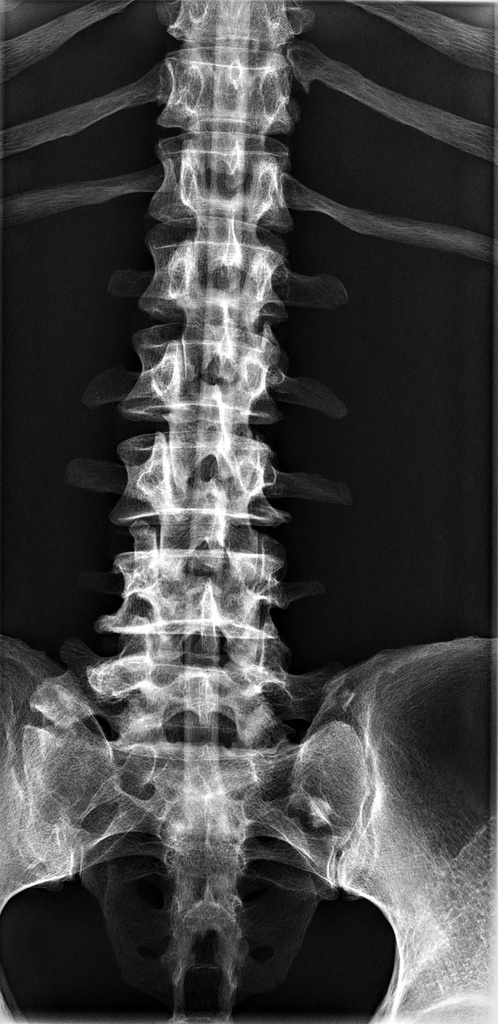

Dieses weltweit einmalige Phantom bietet erstklassige Übungsmöglichkeiten für die Lagerungs- und Einstelltechnik in der Projektions-Radiographie und gehört eigentlich zur Grundausstattung jeder Röntgen-Ausbildungsstätte. Das Phantom enthält ein natürliches menschliches Skelett sowie die Umrisse von Kehlkopf, Lunge, Herz und Nieren (Organe erscheinen als Schatten auf den Röntgenbildern), dadurch können mit dem Phantom echte Röntgenaufnahmen wie beim Patienten gemacht werden. Durch die Verwendung des echten Skeletts können Leitstrukturen im Knochen erkannt werden, was bei Kunststoffskeletten nicht möglich ist. Bei der Montage des Phantoms wird besonderer Wert auf die Darstellung der Gelenkspalte gelegt. Die Gelenke sind voll beweglich montiert, und ermöglichen die Lagerung in den normalen Röntgenpositionen (z.B. Froschposition, Pro- und Supination des Unterarms). Die Arme können nach oben bewegt werden, so dass das Modell auch für alle knöchernen Untersuchungen im CT verwendet werden kann. Bei jedem Phantom handelt es sich um ein handgefertigtes Unikat, welches sich in Größe und Ausführung unterscheiden kann. Je nach Modell können pathologische Befunde vorhanden sein, die äußere Erscheinung kann sich je nach Größe des Modells unterscheiden. Die neue Ausführung dieses Modells wurde in Zusammenarbeit mit einer namhaften deutschen Schule für Med. Techn. Radiologieassistenten komplett überarbeitet und erfüllt alle Anforderungen für die Ausbildung. Der Verkauf dieses Phantoms erfolgt nur gegen Nachweis der medizinischen Verwendung. Natürliche Größe.